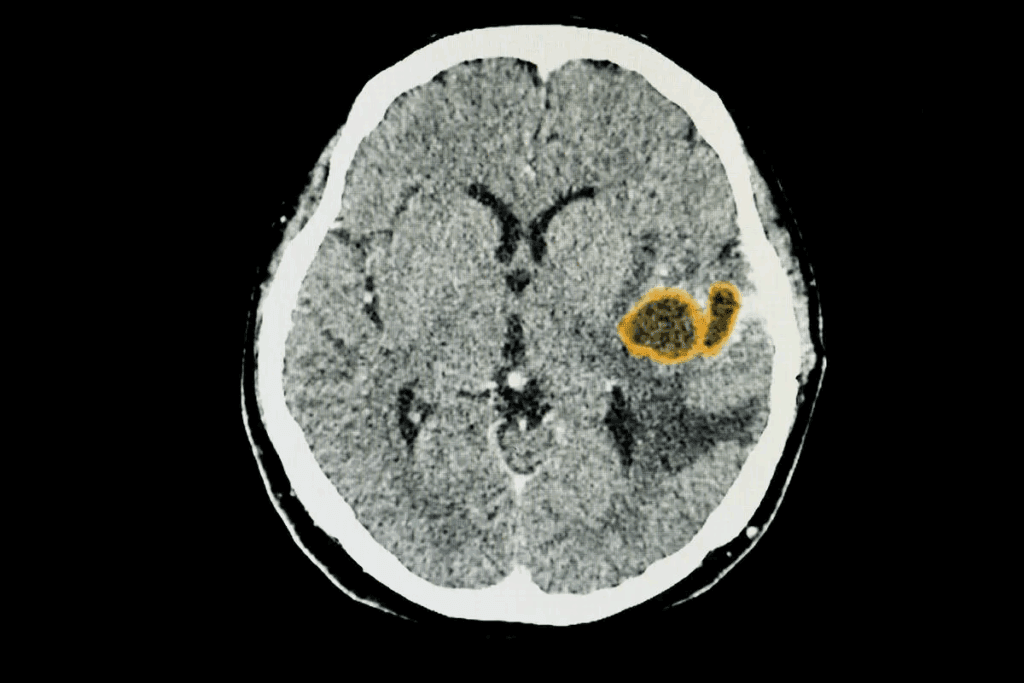

Vascular Issues and Strokes

Vascular problems, like strokes, are another big cause of brain lesions. Strokes can damage brain tissue, causing lesions. The size and location of these lesions affect brain function.

Ischemic Lesions

Ischemic lesions happen when a part of the brain doesn’t get enough blood. This is often due to a stroke or problems with blood vessels. These lesions can cause brain tissue to die and lead to neurological problems.